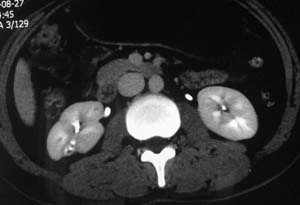

以下是引用子期在2010-3-19 20:47:00的发言:[br]血管畸形的ct增强应该有明显强化,本例并不相符合。本例双肾局部的略低密度影,累及肾盂,局部皮质明显变薄、内陷,增强扫描有轻度的强化,应考虑为炎性病变,患者为年轻男性,累及双肾的感染以结核较常见,可以没有明显的临床症状,尿中有时候也并不能查出什么;肾脓肿常有明显感染中毒症状,本例不符,另外一般的肾盂肾炎或肾小球肾炎通过小便就可确诊,其它还不能排除的是黄色肉芽肿性肾盂肾炎,然而单凭ct一般也很难鉴别。